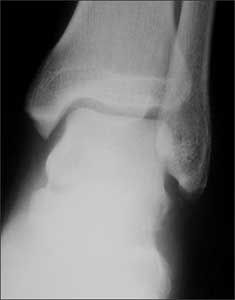

(Answer on next page.)Right ankle pain after a basketball injury: The frontal view of the ankle reveals soft tissue swelling that is predominantly lateral (A, yellow arrow). A small ossific fragment is evident distal to the lateral malleolus (A, white arrow); close inspection shows this to be well-corticated. The remainder of the osseous structures are intact. The lateral view reveals a joint effusion in the talotibial joint (B, arrow); no fractures are visible. In the oblique view (C), the osseous structures appear intact.

The well-corticated ossific fragment is consistent with an old injury, but it is in the region that is now extremely tender. The joint effusion indicates that the current injury is severe. However, this is a nonspecific finding; joint effusions are seen with fractures and ligament and tendon injuries.